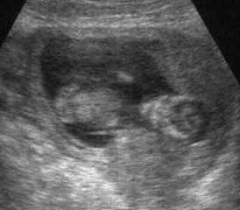

Движения плода на 13 неделе беременности активные и не такие хаотичные, как прежде. Это можно заметить на УЗИ в 13 недель беременности. Малыш ощупывает части своего тела, пуповину, строит гримасы и потягивается. Он еще не видит – глазки прикрыты веками, но уже реагирует на свет. Мимическая мускулатура пока сформирована таким образом, что малыш только хмурится и «сердится». Мышцы, формирующие непроизвольную улыбку, еще недоразвиты.

Каких-либо специальных исследований на этом сроке не требуется. УЗИ в 13 недель беременности назначают только в том случае, если врач видит в этом необходимость, а также тем, кто не успел на первое ультразвуковое исследование.